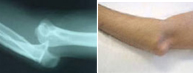

La articulación del codo tiene lugar entre el húmero y el cúbito y radio. Tiene lugar con mayor frecuencia en la segunda década de la vida. La separación traumática entre brazo y antebrazo es frecuente en el ámbito deportivo, especialmente en aquellos deportes que pueden provocar impactos sobre la mano con el codo en extensión. Ello es posible en artes marciales, futbol, baloncesto, y escalada entre otros.Esta lesión no sólo compromete las estructuras óseas sino las ligamentosas y neurovasculares por lo que se requiere un meticuloso estudio en el servicio de urgencias para diagnosticar el grado de afectación tratándolo entonces adecuadamente.

En un primer momento la recolocación del codo en situación anatómica es primordial a través de un suave gesto y en algunas ocasiones bajo anestesia. Si a pesar de la congruencia articular, el codo se presenta inestable, puede ser necesario reforzar la estabilidad ósea con una intervención quirúrgica.